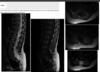

A 14-year-old male presented with months of slowly worsening tingling in his hands. His exam was

intact. Diagnostic work-up included an MRI of the cervical and thoracic spine (figure). What is the most

likely diagnosis?

Ependymoma